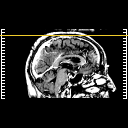

[Home][Help][Clinical] Slice 111

Click on sagittal image to select slice. Click on thin tickmark to change timepoint, or thick tickmark for overlay.